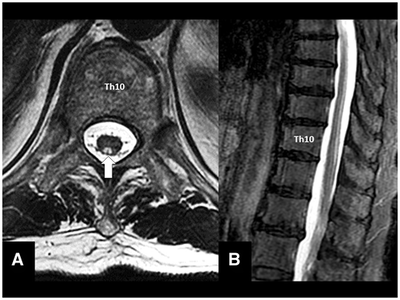

タイトルは「Inverted V sign; subacute combined degeneration of the spinal cord」です。

「Subacute combined degeneration of the spinal cord」は日本語で「亜急性連合性脊髄変性症」と言います。国家試験にも頻出なこの疾患はビタミンB12の欠乏によって発症します。通常対称性に下肢の感覚障害や振動覚の低下、バビンスキー反射陽性が認められますが、不定愁訴の域を抜けきらない診断の難しい疾患です。ビタミンB12の欠乏に伴う疾患は他に「巨赤芽球性貧血」があり、MCV高値を伴う患者を診た際には栄養状態や食事の確認、ビタミンB12の評価が重要です。これに何らかの脱力やしびれなどの症状がある場合には、本症を鑑別疾患の一つとして忘れないようにしましょう。

本症例ではMRIで特徴的な逆Vサインが認められました。ただし本症例のような画像所見を伴う亜急性連合性脊髄変性症はそれほど多いわけではありません(全症例の約20%)。しかしながら後索に特異的に高輝度を示す疾患は他にほとんどないので是非とも覚えていただきたいClinical Pictureの1つです。